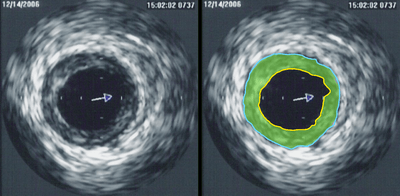

Intravascular ultrasound (IVUS) is a medical imaging methodology using a specially designed catheter with a miniaturized ultrasound probe attached to the distal end of the catheter. The proximal end of the catheter is attached to computerized ultrasound equipment. It allows the application of ultrasound technology, such as piezoelectric transducer or CMUT, to see from inside blood vessels out through the surrounding blood column, visualizing the endothelium (inner wall) of blood vessels in living individuals.[1]

The ultrasound catheter tip is slid in over the guidewire and positioned, using angiography techniques so that the tip is at the farthest away position to be imaged. The sound waves are emitted from the catheter tip, are usually in the 20-40 MHz range, and the catheter also receives and conducts the return echo information out to the external computerized ultrasound equipment which constructs and displays a real time ultrasound image of a thin section of the blood vessel currently surrounding the catheter tip, usually displayed at 30 frames/second image.

The (a) blood vessel wall inner lining, (b) atheromatous disease within the wall and (c) connective tissues covering the outer surface of the blood vessel are echogenic, i.e. they return echoes making them visible on the ultrasound display.

By contrast, the blood itself and the healthy muscular tissue portion of the blood vessel wall is relatively echolucent, just black circular spaces, in the images.

Heavy calcium deposits in the blood vessel wall both heavily reflect sound, i.e. are very echogenic, but are also distinguishable by shadowing. Heavy calcification blocks sound transmission beyond and so, in the echo images, are seen as both very bright areas but with black shadows behind (from the vantage point of the catheter tip emitting the ultrasound waves).